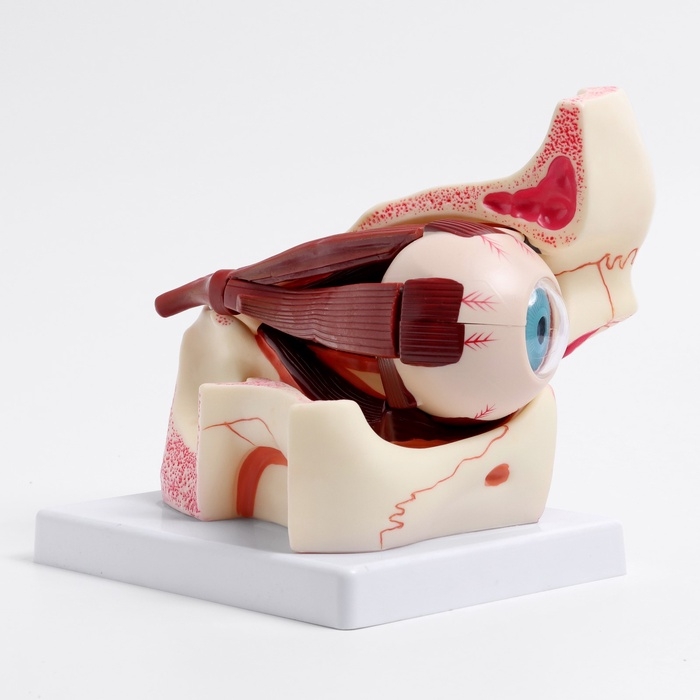

Анатомические модели

ЕКБ 167

No Brand, артикул: 7072352